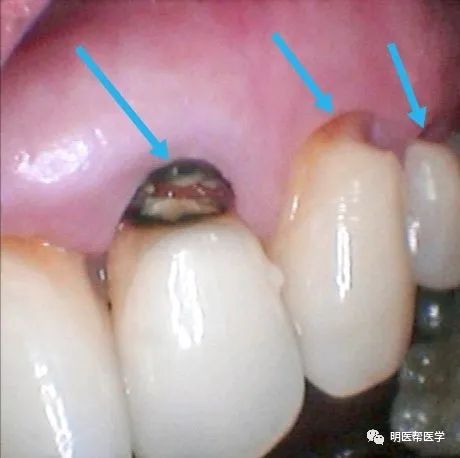

(图七)箭头所指的位置因大面积龋坏做补牙修复,树脂补牙材料变色发黄,补牙材料与牙齿之间出血裂痕。右图是拆除原补牙材料改做全瓷贴面修复。

图七